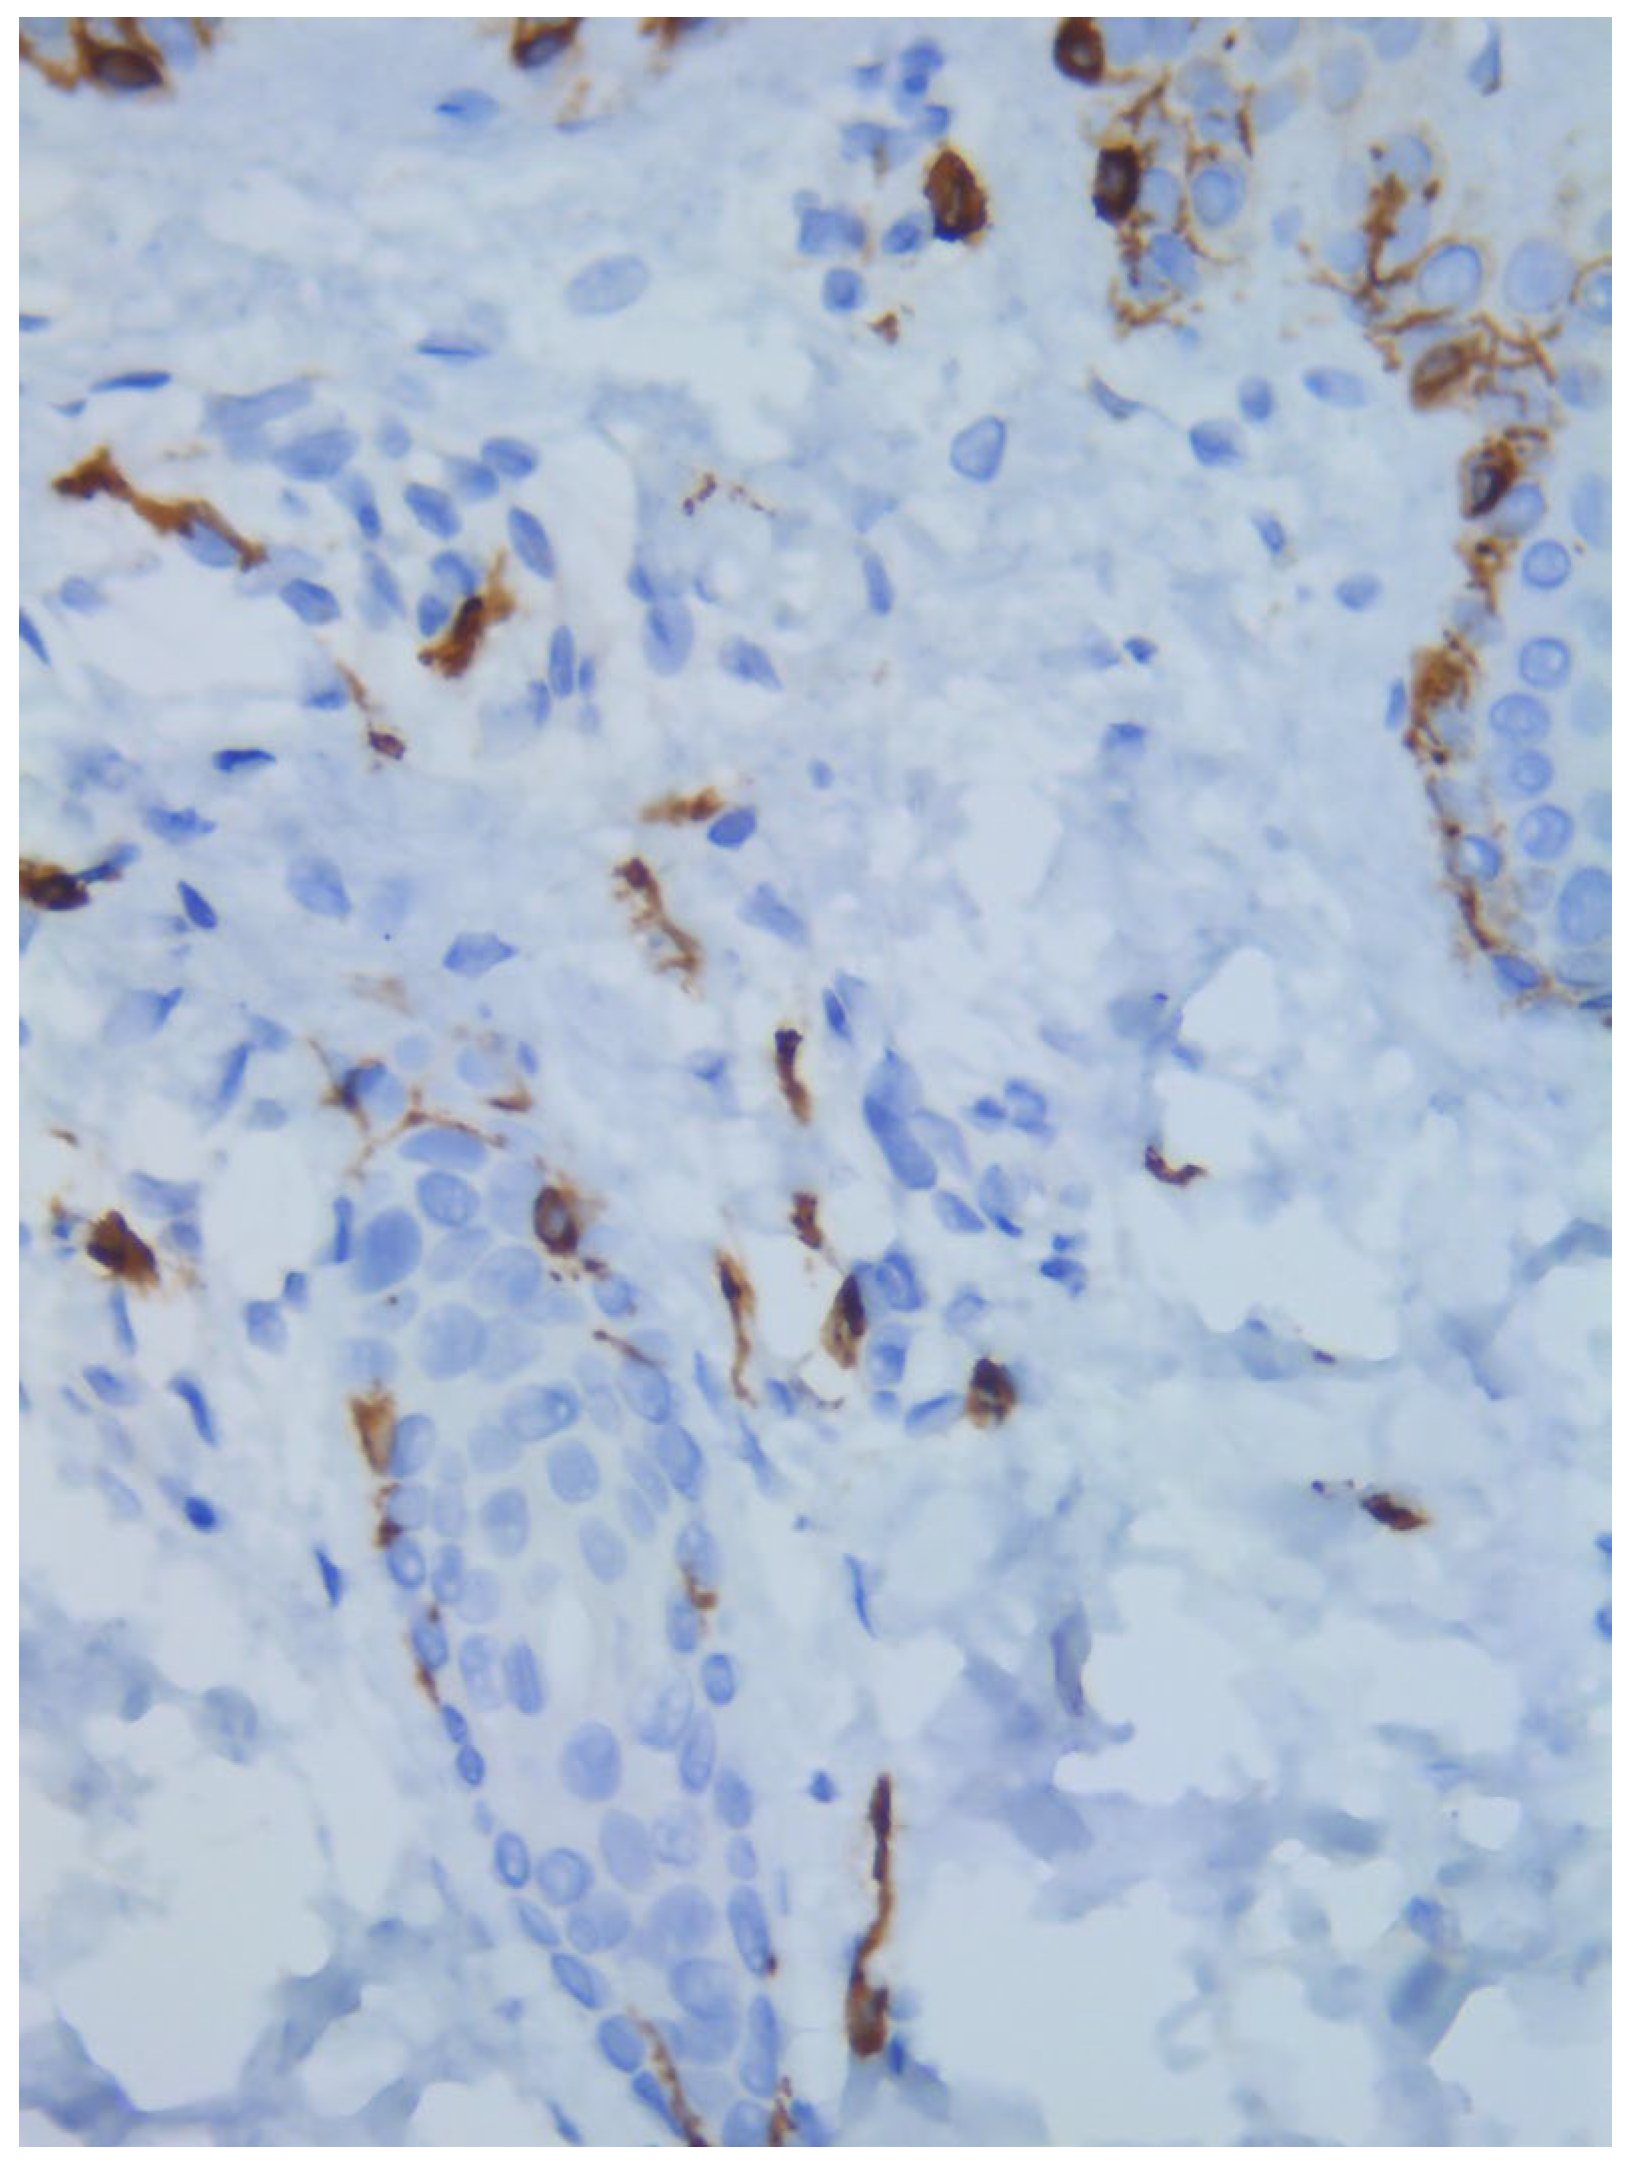

Two skin samples were taken from the upper and lower back, both showing slight, basal cell hyperpigmentation and an inflammatory infiltrate in the superficial dermis (Figure 3). Immunohistochemical stains with tryptase and CD117 showed that the infiltrate included mast cells (Figure 4), mostly with perivascular distribution. Mast cell count in six samples ranged from 11 to 12 mast cells per high-power view (CD117 and tryptase, respectively). The count per mm2 showed 34 mast cells with tryptase and 48 with CD117. C-kitD816V mutation analysis was not available. The bone scintigram did not detect any alterations and an abdominal ultrasound ruled out visceromegaly and only showed 10 mesenteric lymph nodes of non-specific appearance. He is currently under control and receiving oral levocetirizine 5 mg at night.

Figure 4. Mast cell infiltration (CD117, ×400).

Diagnostics 15 01370 g004